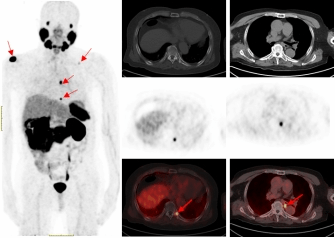

一名75的岁男性患者自2019年确诊前列腺癌后,先后接受过两次内分泌治疗及前列腺癌根治术的综合治疗。在术后两年的复查中发现血PSA持续升高,CT检查和全身骨显像检查均未发现明显异常,医生建议随诊,患者来到成人影视片

附属医院要求进一步检查。经核医学科68Ga-PSMA PET/CT检查后结果显示,双侧肩胛骨、左侧第9后肋、第2腰椎及纵隔淋巴结均已存在癌症转移。